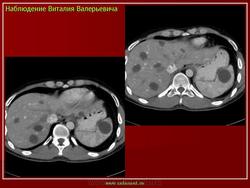

Компьютерную томографию печени выполнили 19(100%) пациентам из группы больных с эхинококкозом в связи с подозрением на паразитарное заболевание и для уточнения изменений печени при уже установленном диагнозе гидатидной болезни. Анализ компьютерных томограмм позволил определить локализацию паразитарных кист в печени в соответствии с сегментарным строением, отношение паразитарного фокуса к паренхиме, капсуле, воротам печени, крупным сосудам, нижней полой вене, соседним органам. При изучении КТ-изображений оценивали форму, наружный и внутренний контуры кисты, толщину и плотность стенки кисты, её содержимое, признаки отложения солей кальция. На компьютерных томограммах выявляли следующие признаки эхинококковых кист: утолщение стенки кисты, неровность ее контуров, расслоение паразитарных мембран, неоднородность содержимого, наличие дочерних кист, перифокальный гиподенсивный ободок.

Плотность содержимого кист варьировала от 9 до 42 ед.Н, нарастала в поздних стадиях эхинококковой болезни. Дочерние кисты имели меньшую плотность, чем плотность материнской кисты. Вариант солидного (умершего) Э в УЗ изображении (2 больных) сопровождался повышением плотности содержимого паразитарной кисты до 36-42 ед.Н. В просвете гидатидомы визуализировались обрывки паразитарных мембран в виде высокоплотных извитых линейных структур, по периферии определялось скорлупообразное обизвестление капсулы (рис а, б). У 4 больных, у которых выявлялся симптом гиперэхогенной дуги с анэхогенной зоной по данным УЗИ, РКТ выявило многокамерное кистозное образование с массивным обизвестлением капсулы (рис 4 ).

Рис 4. Э, РКТ – обизвестление капсулы Э(→)

РКТ была ведущей в дифференциации данной УЗ формы Э с метастатическими поражениями при коллоидном раке толстой кишки. Метастазы отличались внутренней солидной структурой с множественными глыбкообразными включениями солей кальция внутри.